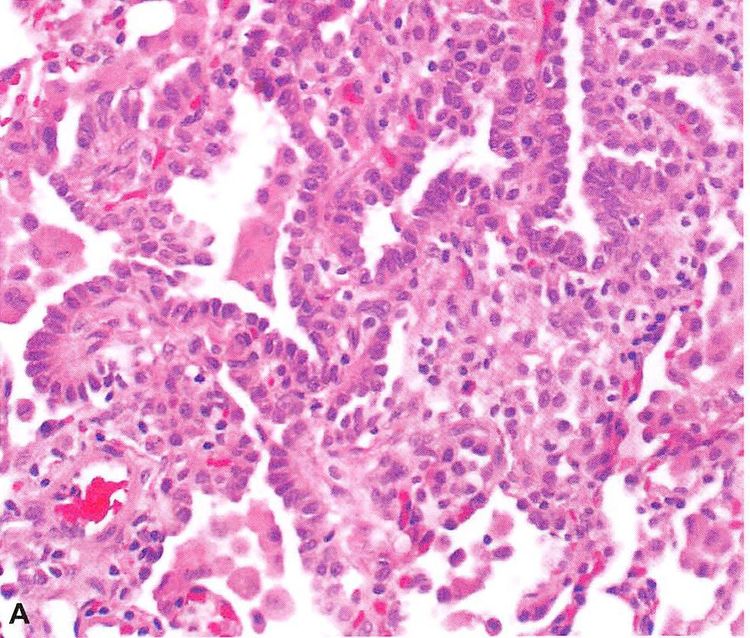

主要研究者之一阿尔伯特·爱因斯坦医学院的基因学教授西蒙·斯皮瓦克(Simon Spivack)说:“这些肺部(上皮)细胞可以存活好几年,甚至几十年,因此随着年龄的增长和吸烟量的增加,所累积的变异越来越多。在所有类型的肺部细胞中,这些细胞最容易出现癌变。”